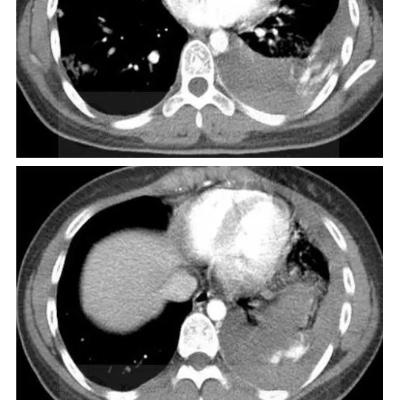

男,45岁,咳嗽,咳痰1个月,发热,盗汗,体重下降5公斤,肺结核病史30年.右肺下叶病变性质待查?